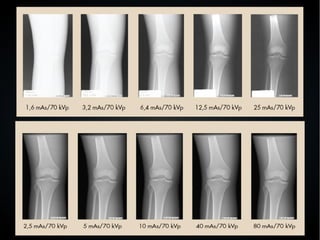

● Radiografía digital (RD) ● Laradiografía digital es más eficaz en tiempo de obtención, espacio y personal requerido que la radiografía convencional. ● La resolución espacial está limitada por el tamaño del píxel en la RD. ● Se obtienen las imágenes digitales utilizando un detector de panel plano (Flat Panel Detector).

• 47.

● RD – FlatPanel ● Indirecto. Contiene láminas de material fluorescente y fotodiodos para hacer la conversión de rX a luz y de luz a señal eléctrica, respectivamente. La señal eléctrica resultante es proporcional a la intensidad de los rX. ● Directo. Utiliza selenio amorfo para convertir la señal de rX directamente a señal eléctrica. Aprovecha de mayor manera la señal de los rX. ● La conversión indirecta minimiza la resolución espacial de la imagen.